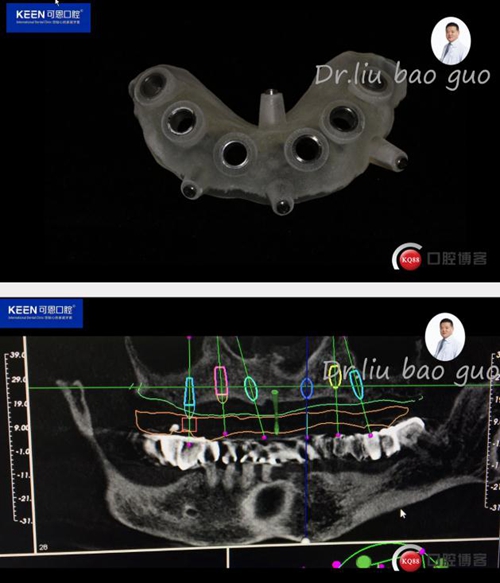

數(shù)字化種植導(dǎo)板設(shè)計(jì)及制作